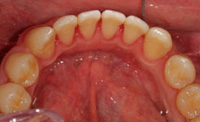

また、お口の中の状態をよりよく知るために、口腔内写真も撮ります。

(5)歯周組織検査・再評価

歯周ポケット(歯と歯ぐきの間)の深さや、出血、歯が動いていないかなどを調べます。

![]()